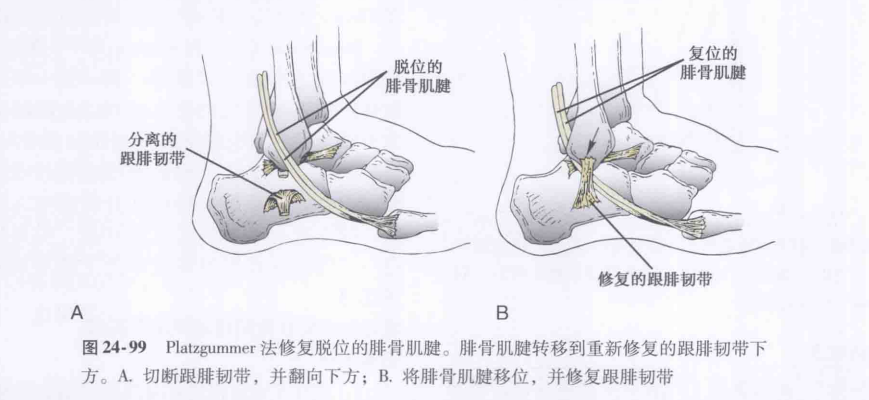

⑤肌腱重排法。

图源:Coughlin M,Saltzman C,Anderson R,et al. 曼氏足踝外科学 [M]. 第 9 版. 唐康来, 徐林, 译. 北京: 人民卫生出版社,2015:1915.